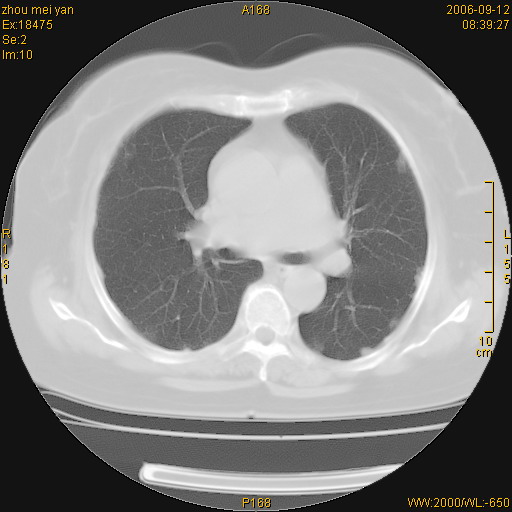

患者、女、55岁。因心率失常住院检查ct发现胸部多发结节。腹部b超肝、胆、胰、脾、肾、子宫附件未见异常。无结核病史,无粉尘接触史。请大家来会诊。谢谢!

病变位于胸膜,多发结节,边界清楚,内见小结节状钙化。其它未见异常。

多发胸膜表面的结节,基本对称,部分有钙化。首先考虑类风湿性胸膜结节,次则考虑结核性胸膜炎后遗之胸膜结节状增厚、钙化。

双侧胸膜多发结节,形态不规则,边缘较清楚,每一个结节中心似乎都有钙化点的特征,与胸膜广基相切。临床无结核病史,无粉尘接触史。

影像表现十分有特点:双侧肋胸膜及膈胸膜广泛散在分布大小在2至6mm左右,较大病灶中心可见钙化。

双侧肋胸膜及膈胸膜广泛散在分布大小不等结节影,较大病灶中心可见钙化。